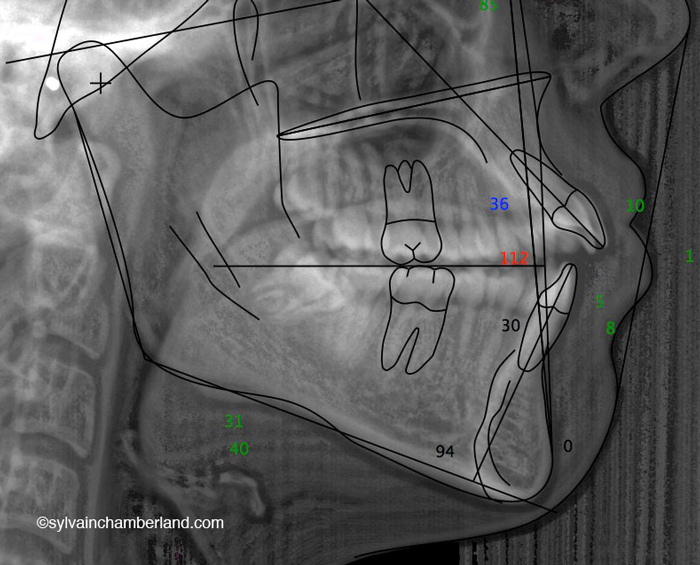

Sur la radiographie de gauche, la plus grande barre horizontale représente la 2e vertèbre cervicale. Normalement, l’angle goniaque est situé à cette hauteur. La résorption des condyles a causé un raccourcissement de la branche montante de sorte que l’angle goniaque se trouve à hauteur de la 1re vertèbre cervicale. La petite barre horizontale indique la largeur du tractus oropharyngé. il faut avoir normalement 10 à 15 mm. Dans ce cas, il y a à peine 5 mm de largeur.

Remarquez la distance entre les racines des dents postérieures supérieures et le palais comparativement au cas suivant où cette distance est augmentée.

Dans ce cas-ci la béance s’explique par un excès vertical du maxillaire. Observez, sur la radiographie céphalométrique de gauche, la grande distance entre les racines des dents postérieures supérieures et le palais. C’est l’indication d’un excès vertical. La longueur de la branche montante est normale et l’angle goniaque est à la hauteur de la 2e vertèbre cervicale.

Vous pouvez aussi comparé avec le tracé céphalométrique du cas précédent avec résorption des condyles. Il est facile de constater que l’angle goniaque est au niveau de C2 et que l’espace oropharyngé est plus large.

Ces deux cas illustrent une malocclusion avec béance antérieure, mais deux étiologies totalement différentes. Dans le 1er cas, la béance antérieure s’explique par la résorption condylienne. Dans le 2e cas, la béance s’explique par un excès vertical du maxillaire supérieur.

Le cas avec résorption a nécessité le remplacement des articulations par des prothèses totales customisées.

Le 2e cas a subi une chirurgie orthognathique bimaxillaire conventionnelle avec repositionnement supérieur du maxillaire, ostéotomie mandibulaire et génioplastie.